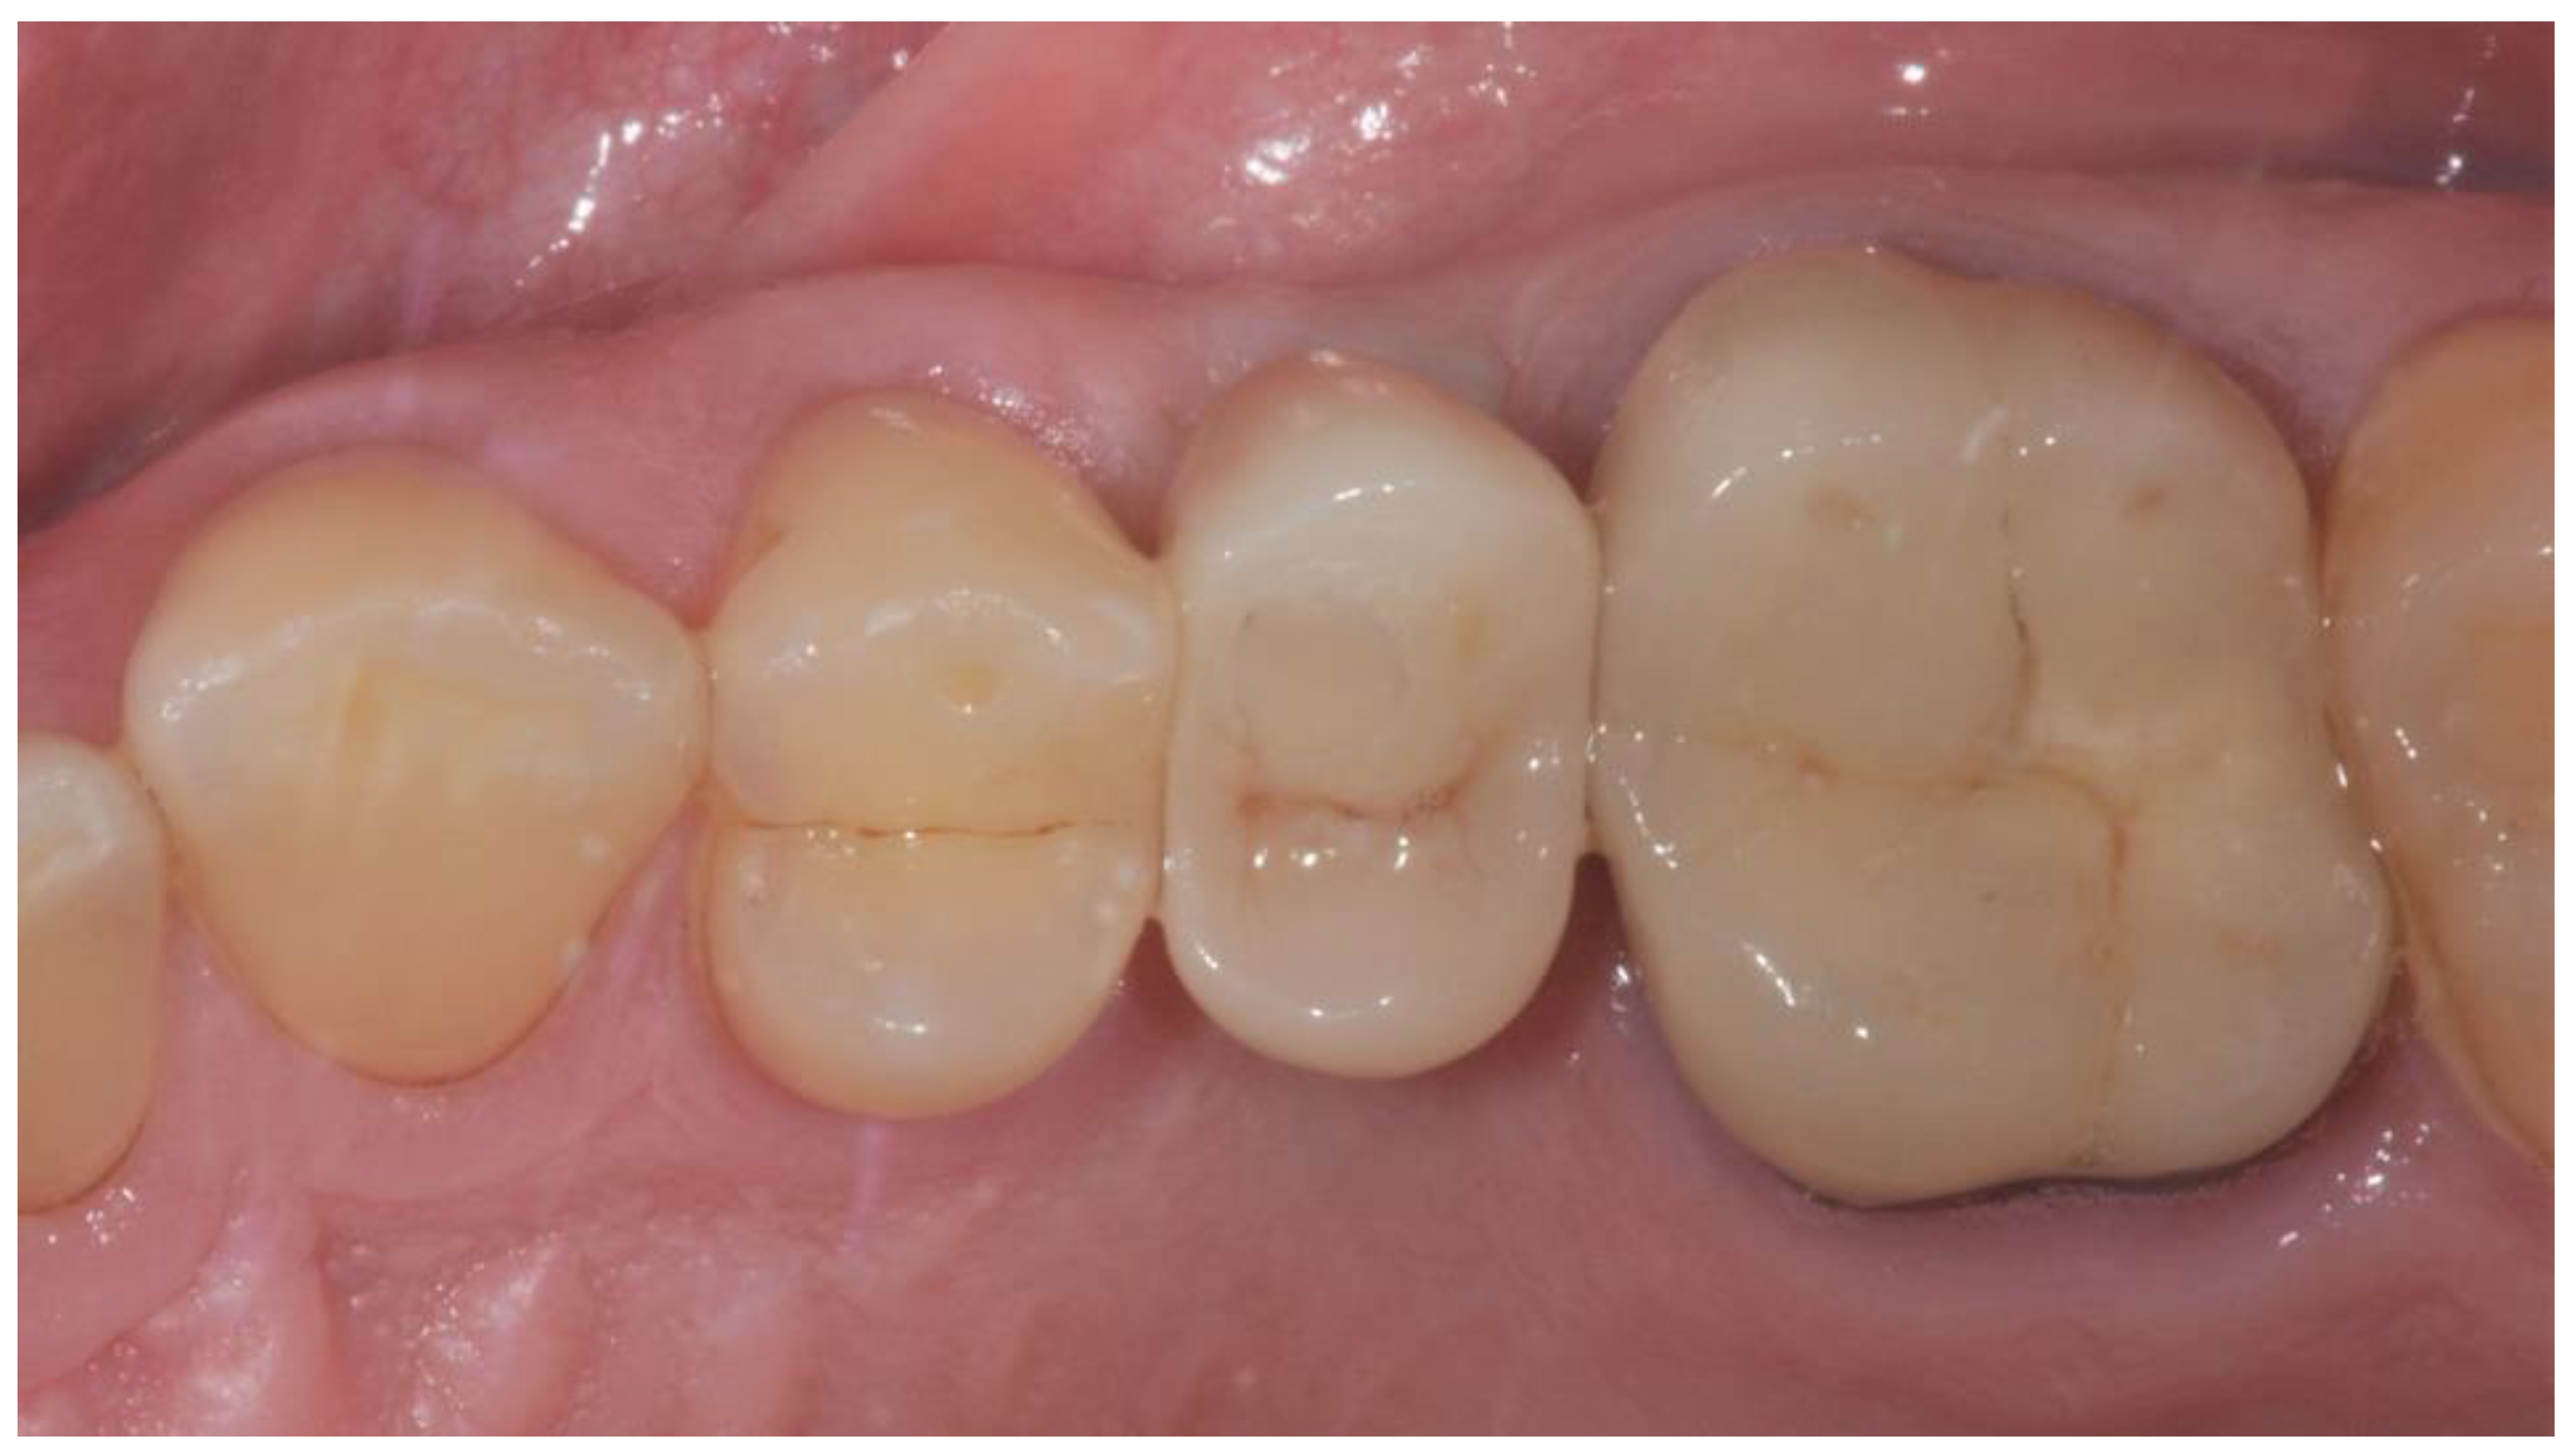

2. Materials and Methods

2.3. Prosthetic Protocol